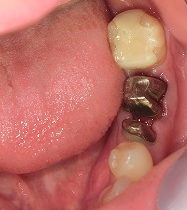

より割れにくくキレイな歯に